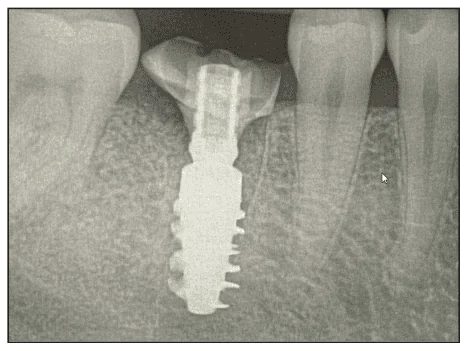

The custom healing abutment was fabricated chairside utilizing a metal temporary abutment and composite (Figure 3). Custom healing abutments aid in the support of soft-tissue contours and tend to be more aesthetic with better contours and improved contact (Figure 4). Plus, areas experience less food impaction when restored. The soft-tissue anatomy was supported with 2 to 3 mm of composite, ensuring the material would not impinge on the socket’s bone. A radiograph was taken as part of the standard procedure (Figure 5).